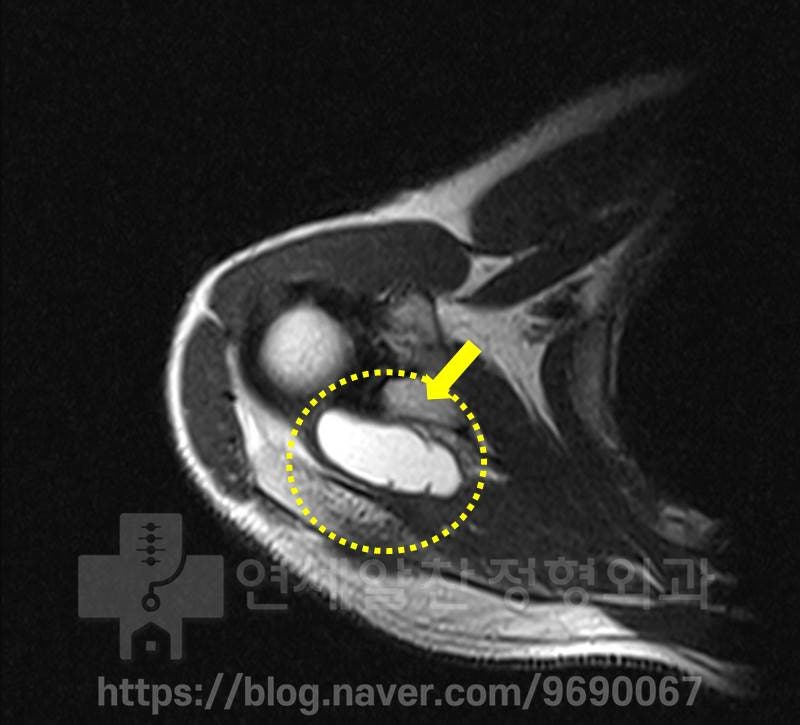

다른 각도의 MRI 상에서도 커다란 어깨물혹이 관찰됩니다. 이 부위에서의 상부관절와순의 손상은 확인되지 않습니다.

역시 MRI 상 어깨 물혹이 관찰됩니다. 빨간색으로 표시된 부위에서 약간의 상부관절와순의 손상 흔적이 관찰되었으나 현재는 치유된 상태로 판단됩니다. 이학적 검사를 하였을 때 슬랩(SLAP) 을 의심할 만한 소견은 보이지 않았으며 극상근, 극하근의 근력약화에 대한 이학적 검사는 양성 반응을 보였습니다. 이 환자의 경우 관절와순 손상이 미미하였으며 거의 치유된 상태로 판단되며 커다란 어깨 물혹에 의한 증상으로 판단되었습니다. 그래서 초음파 유도하에 주사기를 통해 물혹을 제거하기로 하였습니다.